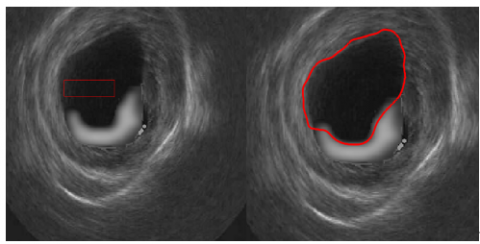

5.5 Results of MRI and echographic images

The algorithm's effectiveness depends on the initial position of the level set curve and the defined parameters, with bad choices potentially leading to inaccurate segmentations. In cardiac MRIs, low contrast transitions complicate contour evolution, especially in poorly defined anatomical areas.

After several attempts, we successfully segmented some cardiac MRI and echographic images.

In Figure 11, we present the segmentation results applied to both MRI and ultrasound images, obtained using the DRLS (Distance Regularized Level Set) algorithm. The parameters used to segment MRI and ultrasound images were selected after several tests to achieve precise and rigorous segmentation that accurately defines the target contour.

(a) The cardiac ultrasound image

(b) The cardiac MRI image

(c) The ultrasound image

Figure 11. Segmentation results of MRI and echographic images

Using the parameters μ=0.04, λ=5, α=-1, σ=5 and 200 iterations, the segmentation of the cardiac ultrasound image demonstrates the effectiveness of the DRLSE algorithm in accurately detecting the edges of the cardiac wall, even in the presence of noise (Figure 11(a)). The moderate regularization ensured by μ=0.04 preserves the details of the contours, while λ=5 strikes a balance between contour attraction and stability. The parameter α=−1 enhances the algorithm’s ability to handle noisy regions, and σ=5 reduces noise while maintaining critical transitions in the image.

The set of parameters μ, λ, α, and σ allows for accurate and robust segmentation, proving the adaptability of the algorithm to the challenges posed by ultrasound images.

For the MRI heart image, the segmentation with the parameters μ=0.2, λ=1, α=1, σ=6, and 200 iterations demonstrates the DRLSE algorithm's ability to effectively highlight contrasts between different tissues, allowing for precise localization of the targeted contour (Figure 11(b)).

For the image shown in Figure 11(c), segmentation with the parameters μ =0.2, λ =5, α =-1, σ =6, and 200 iterations produces a satisfactory result. The segmented contours are both sufficiently sharp and well defined, while maintaining a certain smoothness that prevents the influence of noise. These parameter values provide an optimal compromise between fidelity to the image intensity data and contour smoothness, resulting in accurate segmentation while minimizing imperfections due to artifacts or noise.

However, the approach based on local information (gradients) has limitations when dealing with complex structures or artifacts, highlighting the need for global information integration to achieve accurate segmentation.